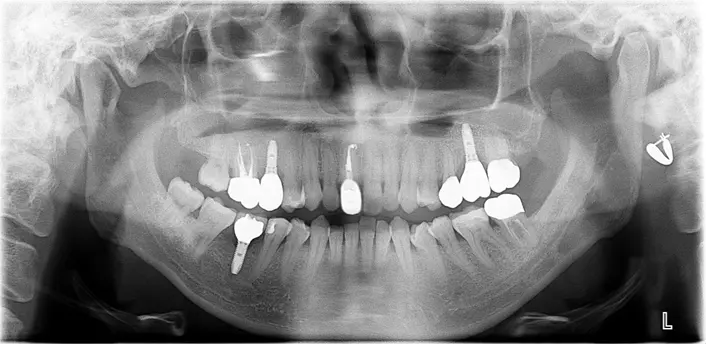

| 治療ケース |

上顎左右サイナスリフトPRP使用 上下顎前歯GBRベニアグラフト,PRP使用 上顎8本12歯インプラント 下顎7本12歯インプラント 上部構造ハイブリッドセラミック(咬合確保・審美歯科) |

| 症状 | 事故により歯を喪失され、体調不良もあり歯科医院への通院ができなかった。 |

| 治療結果 | 咬合を確保した事により、しっかり食事も摂取しやすくなり、体調良好に繋がった。審美的にも改善し見た目も健康になられ、エイジングケアに繋がった。 ※治療結果は患者様によって個人差があります。 |

| 治療方法 | 口腔の健康が全身の健康に繋がることをしっかりとお伝えし残存歯すべて抜歯、前歯部上顎洞に対して大がかりな骨造成を経てインプラント治療により咬合を確保した。 |

| 治療費用(税込) | 上顎左右サイナスリフト:528,000円(税込)

| 治療期間 | 2年 |